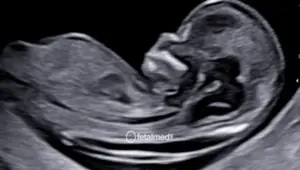

O ultrassom morfológico de segundo trimestre é o exame mais completo para avaliação da anatomia fetal. Realizado idealmente entre 20 e 24 semanas de gestação, ele permite visualizar todos os órgãos e sistemas do bebê com alto nível de detalhamento.

É considerado o exame de referência para detecção de malformações fetais e para o planejamento obstétrico da segunda metade da gestação.

O período ideal é entre 20 e 24 semanas de gestação. Nesta fase, o feto tem tamanho suficiente para que todos os órgãos sejam avaliados com precisão, e ainda há quantidade adequada de líquido amniótico para obter boas imagens.